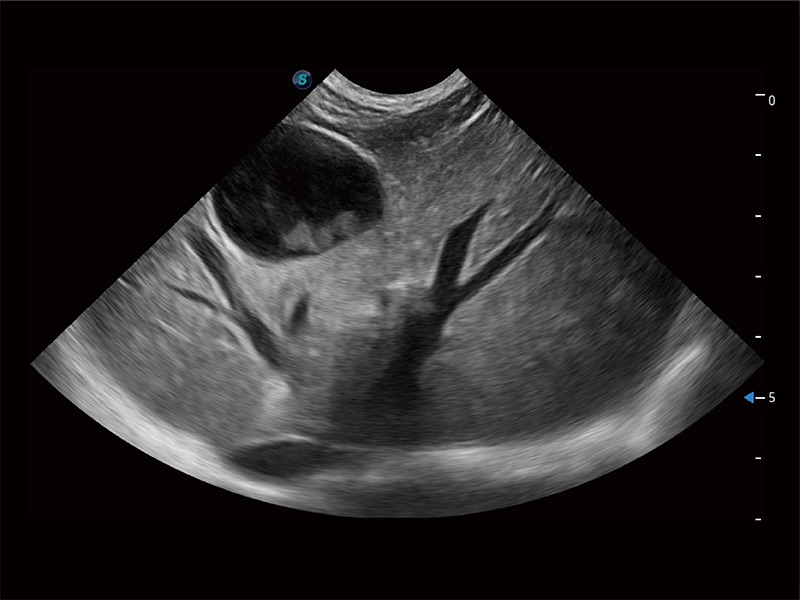

一鍵自動識別膀胱壁及自動測量膀胱容積,不受膀胱形狀和大小的限制,幫助醫(yī)生快速精準(zhǔn)獲得測量的數(shù)據(jù)。